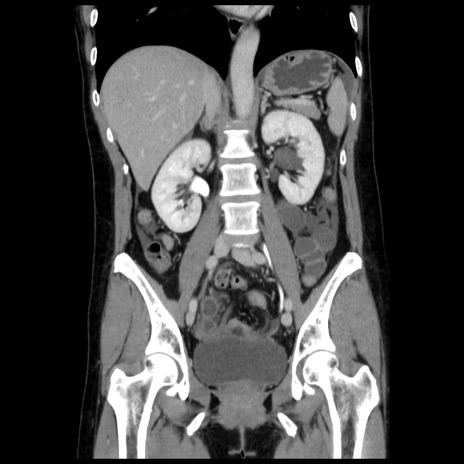

症例10(冠状断像)

【症例】 50歳代女性

【主訴】 腹痛

【現病歴】前日生レバーを食べた。今朝に排便あり。 昼前に突然発症の腹痛を生じ、当院救急外来を受診した。

【既往歴】 子宮筋腫にてで子宮全摘後

【身体所見】 意識清明、腹部:平坦、軟、下腹部やや左を中心に圧痛・反跳痛あり、筋性防御あり

【データ】WBC 7800、CRP 0.07